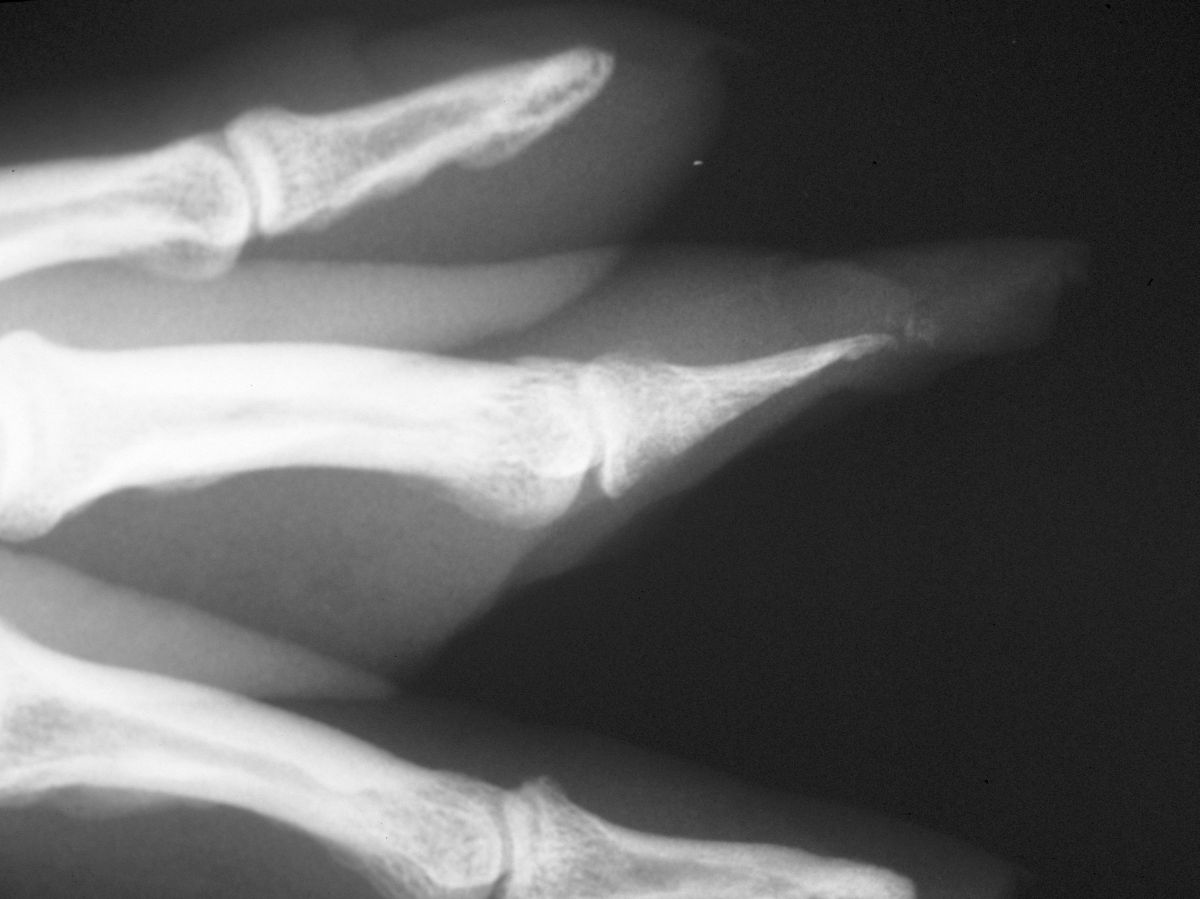

| Case

3. This gentleman sustained partial amputations of all fingers in an industrial press. His index finger was the only digit with a potentially salvageable fingertip. |

| Distal phalanx

fracture stabilization. Pins were placed to protrude

proximally in anticipation of flap cover. |